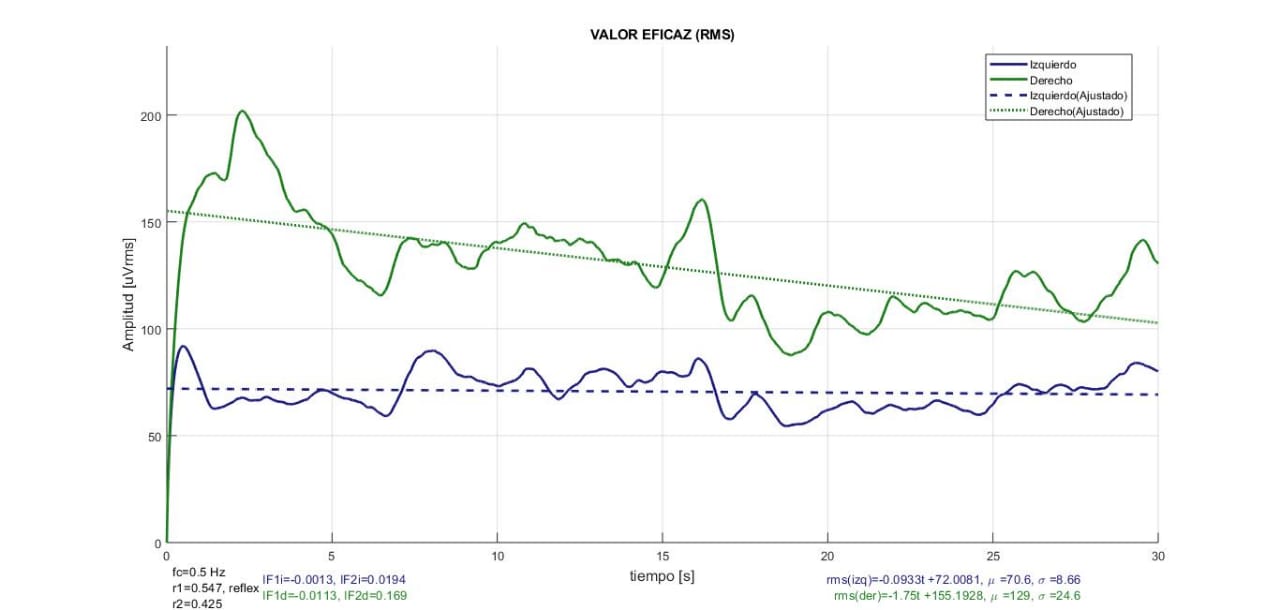

Valor RMS de señal EMGS cruda registrada durante contracción isométrica en oclusión centrica (OC), (Laboratorio de fisiología oral, 2019)

La repetibilidad de las variables extraídas de la señal EMGS basadas en la estimación de la amplitud y la densidad de la potencia espectral, como RMS, ARV, MNF y MDF, mejora si se utiliza una metodología de estandarización y normalización como la sugerida por [26-30]. Sin embargo, no siempre es viable.

La repetibilidad de la variable ARV dentro de cada sujeto y entre sujetos mejora al aumentar la distancia inter-electrodos (IED). Pero es aplicable solo si se realiza contracción isométrica controlada a través de un sistema de bioretroalimentación que incluya un sensor de fuerza de mordida.